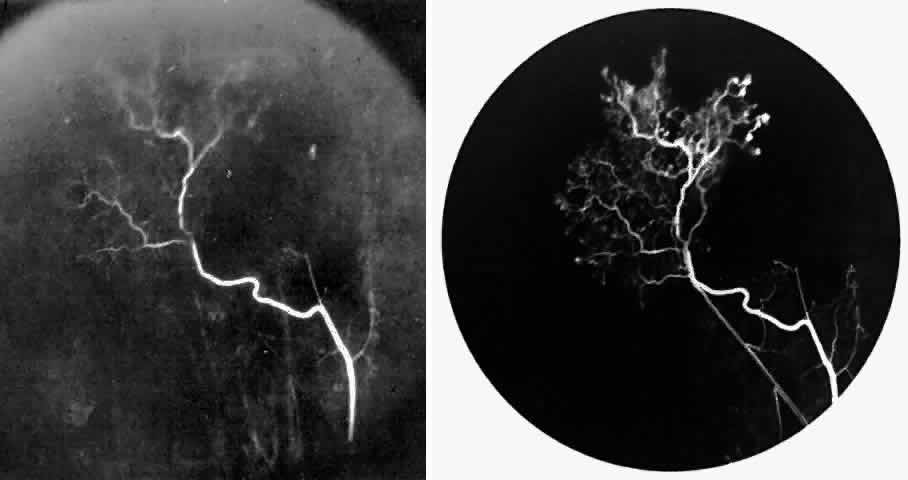

STAGE III: PRERETINAL NEOVASCULARIZATION (PROLIFERATIVE SICKLE RETINOPATHY). “Sea fan”-shaped neovascularization typically develops on the venular side of an arteriolar-venular anastomosis, mimicking the normal development of retinal capillaries (Fig. 24).125 A lowered oxygen tension and angiogenic factors released on the venular side may be the stimulus for neovascular growth.125,126 In most instances, the direction of growth is toward the ora serrata, from the perfused retina toward the nonperfused retina. Presumably, this represents an abortive attempt to revascularize the nonperfused retina, initiated by vasoproliferative factors.

Fig. 24. A. Photograph of the peripheral retina, demonstrating several small fibroglial membranes. B. Fluorescein angiogram corresponding to A, showing multiple arteriolar-venular anastomoses with early sea fan formation. C. Photograph of the same area 2 years later demonstrates more fibroglial membranes. D. Fluorescein angiogram corresponding to C shows new sea fans caused by an arteriolar-venular anastomosis (curved arrow). Large arrow (A through D) identifies corresponding arteriolar bifurcation.

The characteristic neovascular lesions of PSR are called sea fans because they resemble the marine invertebrate Gorgonia flabellum.70 They tend to occur more commonly in the temporal periphery, but they have been reported to occur in the temporal macula in the presence of extensive nonperfusion.130,133 Initially they grow on the surface of the retina, but they often become elevated into the vitreous and adhere to a partially detached posterior hyaloid.114 It may be difficult to visualize small sea fans ophthalmoscopically; however, fluorescein angiography clearly demonstrates leakage of dye into the vitreous (Fig. 25). The feeding arteriole is usually more tortuous than the draining venule (Fig. 26). Early on, the neovascular lesion is fed by a single arteriole and drained by a single venule, but with time, additional arterioles and venules become arborized within the lesion (Fig. 27).129 Growth of the sea fan often occurs circumferentially, rather than radiallyÜmh- 1Ý, toward the ora serrata. Progressive circumferential growth may lead to neovascular lesions extending around the entire periphery. As it matures, a white fibroglial mantle often covers the neovascular tissue (Color Plate 2B).

Fig. 25. Fluorescein angiogram of early proliferative sickle retinopathy arising from an arteriolar-venular anastomosis in an area of irregular peripheral capillary border. Note that this area of qualitatively abnormal peripheral capillary border is in the same eye with a qualitatively normal peripheral retinal vasculature, as demonstrated in Figure 23.

Fig. 26. A. Arterial filling phase of the fluorescein angiogram of a sea fan demonstrates tortuosity of the feeding arteriole. B. Early arteriolar-venular filling phase demonstrates straightening of the draining venule. Note that this sea fan is adjacent to the qualitatively normal peripheral retinal vasculature demonstrated in Figure 23.